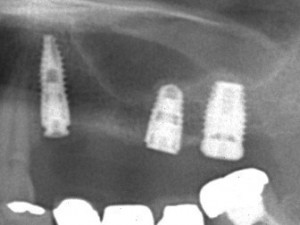

右上3本、左上3本、左下2本のインプラントを埋入。

右上は骨が足りない為サイナスリフトをしてインプラント手術を行いました。

術後のレントゲン写真